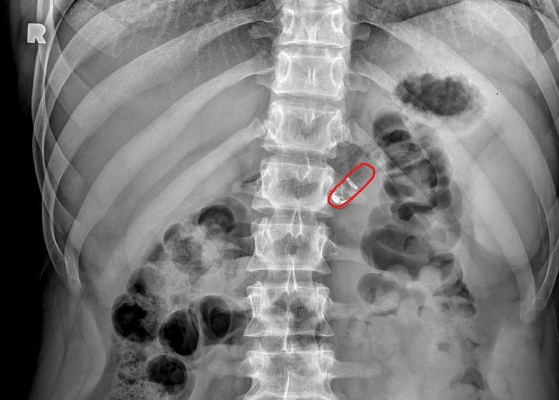

El enfoque de Rani Therapeutics se basa en las propiedades inherentes del tracto gastrointestinal. Un mecanismo de inyección en su píldora está rodeado por una capa sensible al pH que se disuelve a medida que la cápsula se mueve desde el estómago del paciente al intestino delgado. Esto ayuda a garantizar que la píldora comience a inyectarse el medicamento en el lugar correcto en el momento correcto. Una vez allí, los reactivos se mezclan y producen dióxido de carbono, que a su vez infla un pequeño globo que ayuda a crear una diferencia de presión para ayudar a inyectar las agujas cargadas con el fármaco en la pared intestinal. “Así que es una cascada de eventos realmente oportuna que da como resultado la administración de esta aguja”, dijo Imran.

A pesar de su procedimiento algo mecánico, la píldora en sí no contiene metal ni resortes, lo que reduce la posibilidad de una respuesta inflamatoria en el cuerpo. En cambio, las agujas y otros componentes están hechos de polímeros de grado inyectable, que Imran dijo que también se ha utilizado en otros dispositivos médicos. La administración de las inyecciones en la parte superior del intestino delgado también conlleva poco riesgo de infección, ya que la prevalencia del ácido del estómago y la bilis del hígado evita que las bacterias crezcan fácilmente allí.